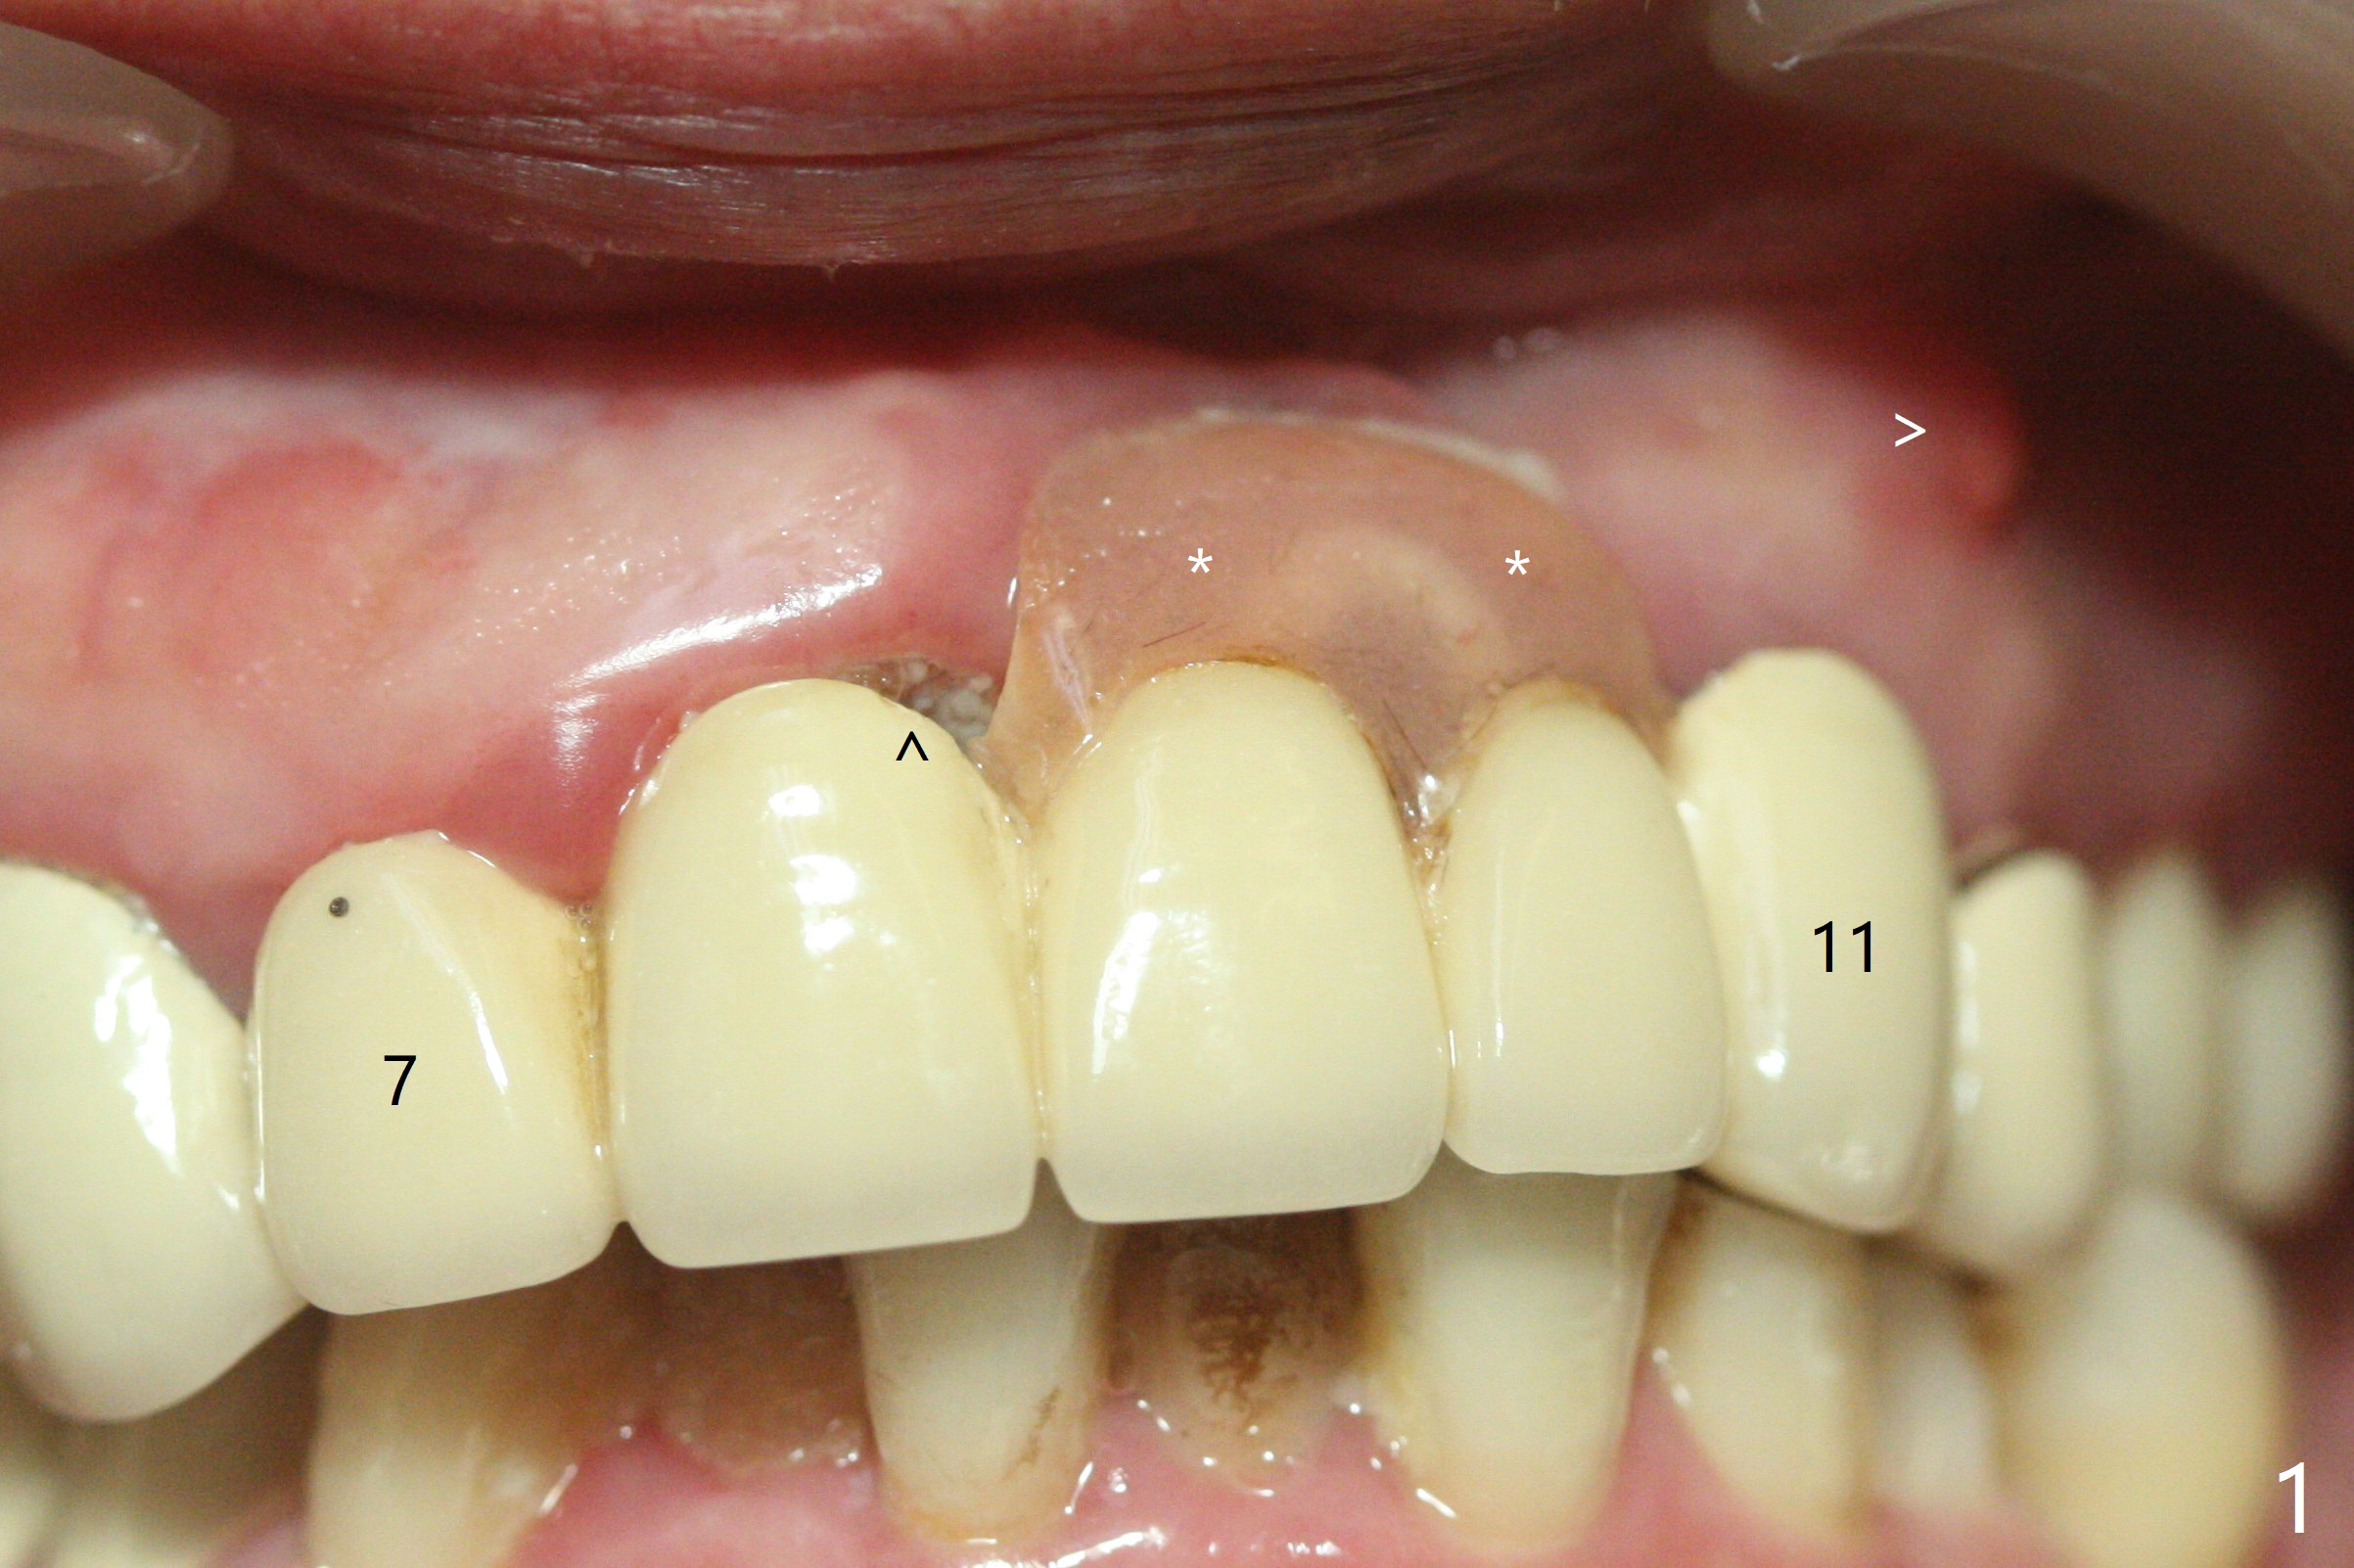

今天来一位57岁女,“前牙桥快掉了” (图一:7-11,桥在尖牙(11)端松动明显),不明白为什么左上中,侧切牙唇侧带有托牙树脂(*),影响局部卫生(^)。全景片(图二),CT(图三)显示刀柄植体,好像没有骨质吸收,但是修复体与基台脱离,树脂大概有美观作用。尖牙根尖瘘道(图一:>),阴影(图三 (B:颊侧),四)表明牙齿似乎无法保留,其余牙齿命运等待桥撤除后决定。琼脂取模,模型已制备,简易stent尚未完成。明天一早病人回来治疗,抽血一管制备骨块和PRF膜。